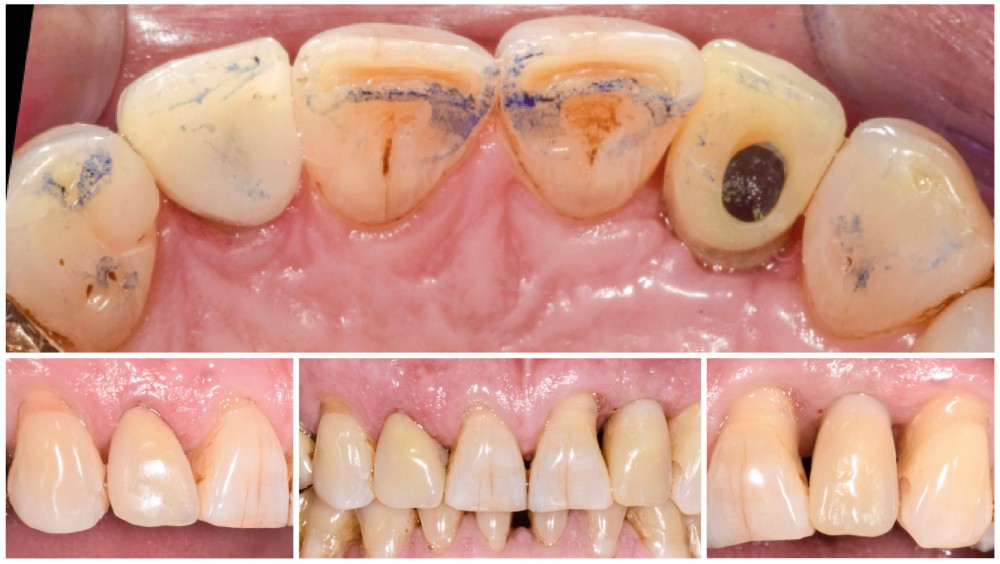

Situation initiale

Un patient de 62 ans se présente en consultation afin de réaliser les coiffes prothétiques des dents 12 et 22. La 12 présente une restauration par prothèse transitoire non adaptée. Un implant au niveau de la 22 a été posé par un autre praticien selon une technique chirurgicale en deux temps. Le praticien a adressé le patient pour la réalisation prothétique. L’option de bridge collé cantilever mono ailette n’avait pas été retenue ou proposée selon une technique chirurgicale en deux temps. Le patient souhaite rétablir l’esthétique et la fonction de ces deux dents uniquement.

Au vu des conditions initiales, il nous apparaît impossible de restaurer une esthétique satisfaisante, notamment au niveau de l’alignement des collets, sans une chirurgie muco-gingivale associée à une réhabilitation des dents antérieures par facettes. En effet, la perte de la 22, associée à une forme triangulaire des dents, a provoqué un non-alignement des collets ainsi que la présence de trous noirs entre les dents 21-22 et 22-23. Cependant, les contraintes exprimées par le patient contre-indiquaient ce traitement.